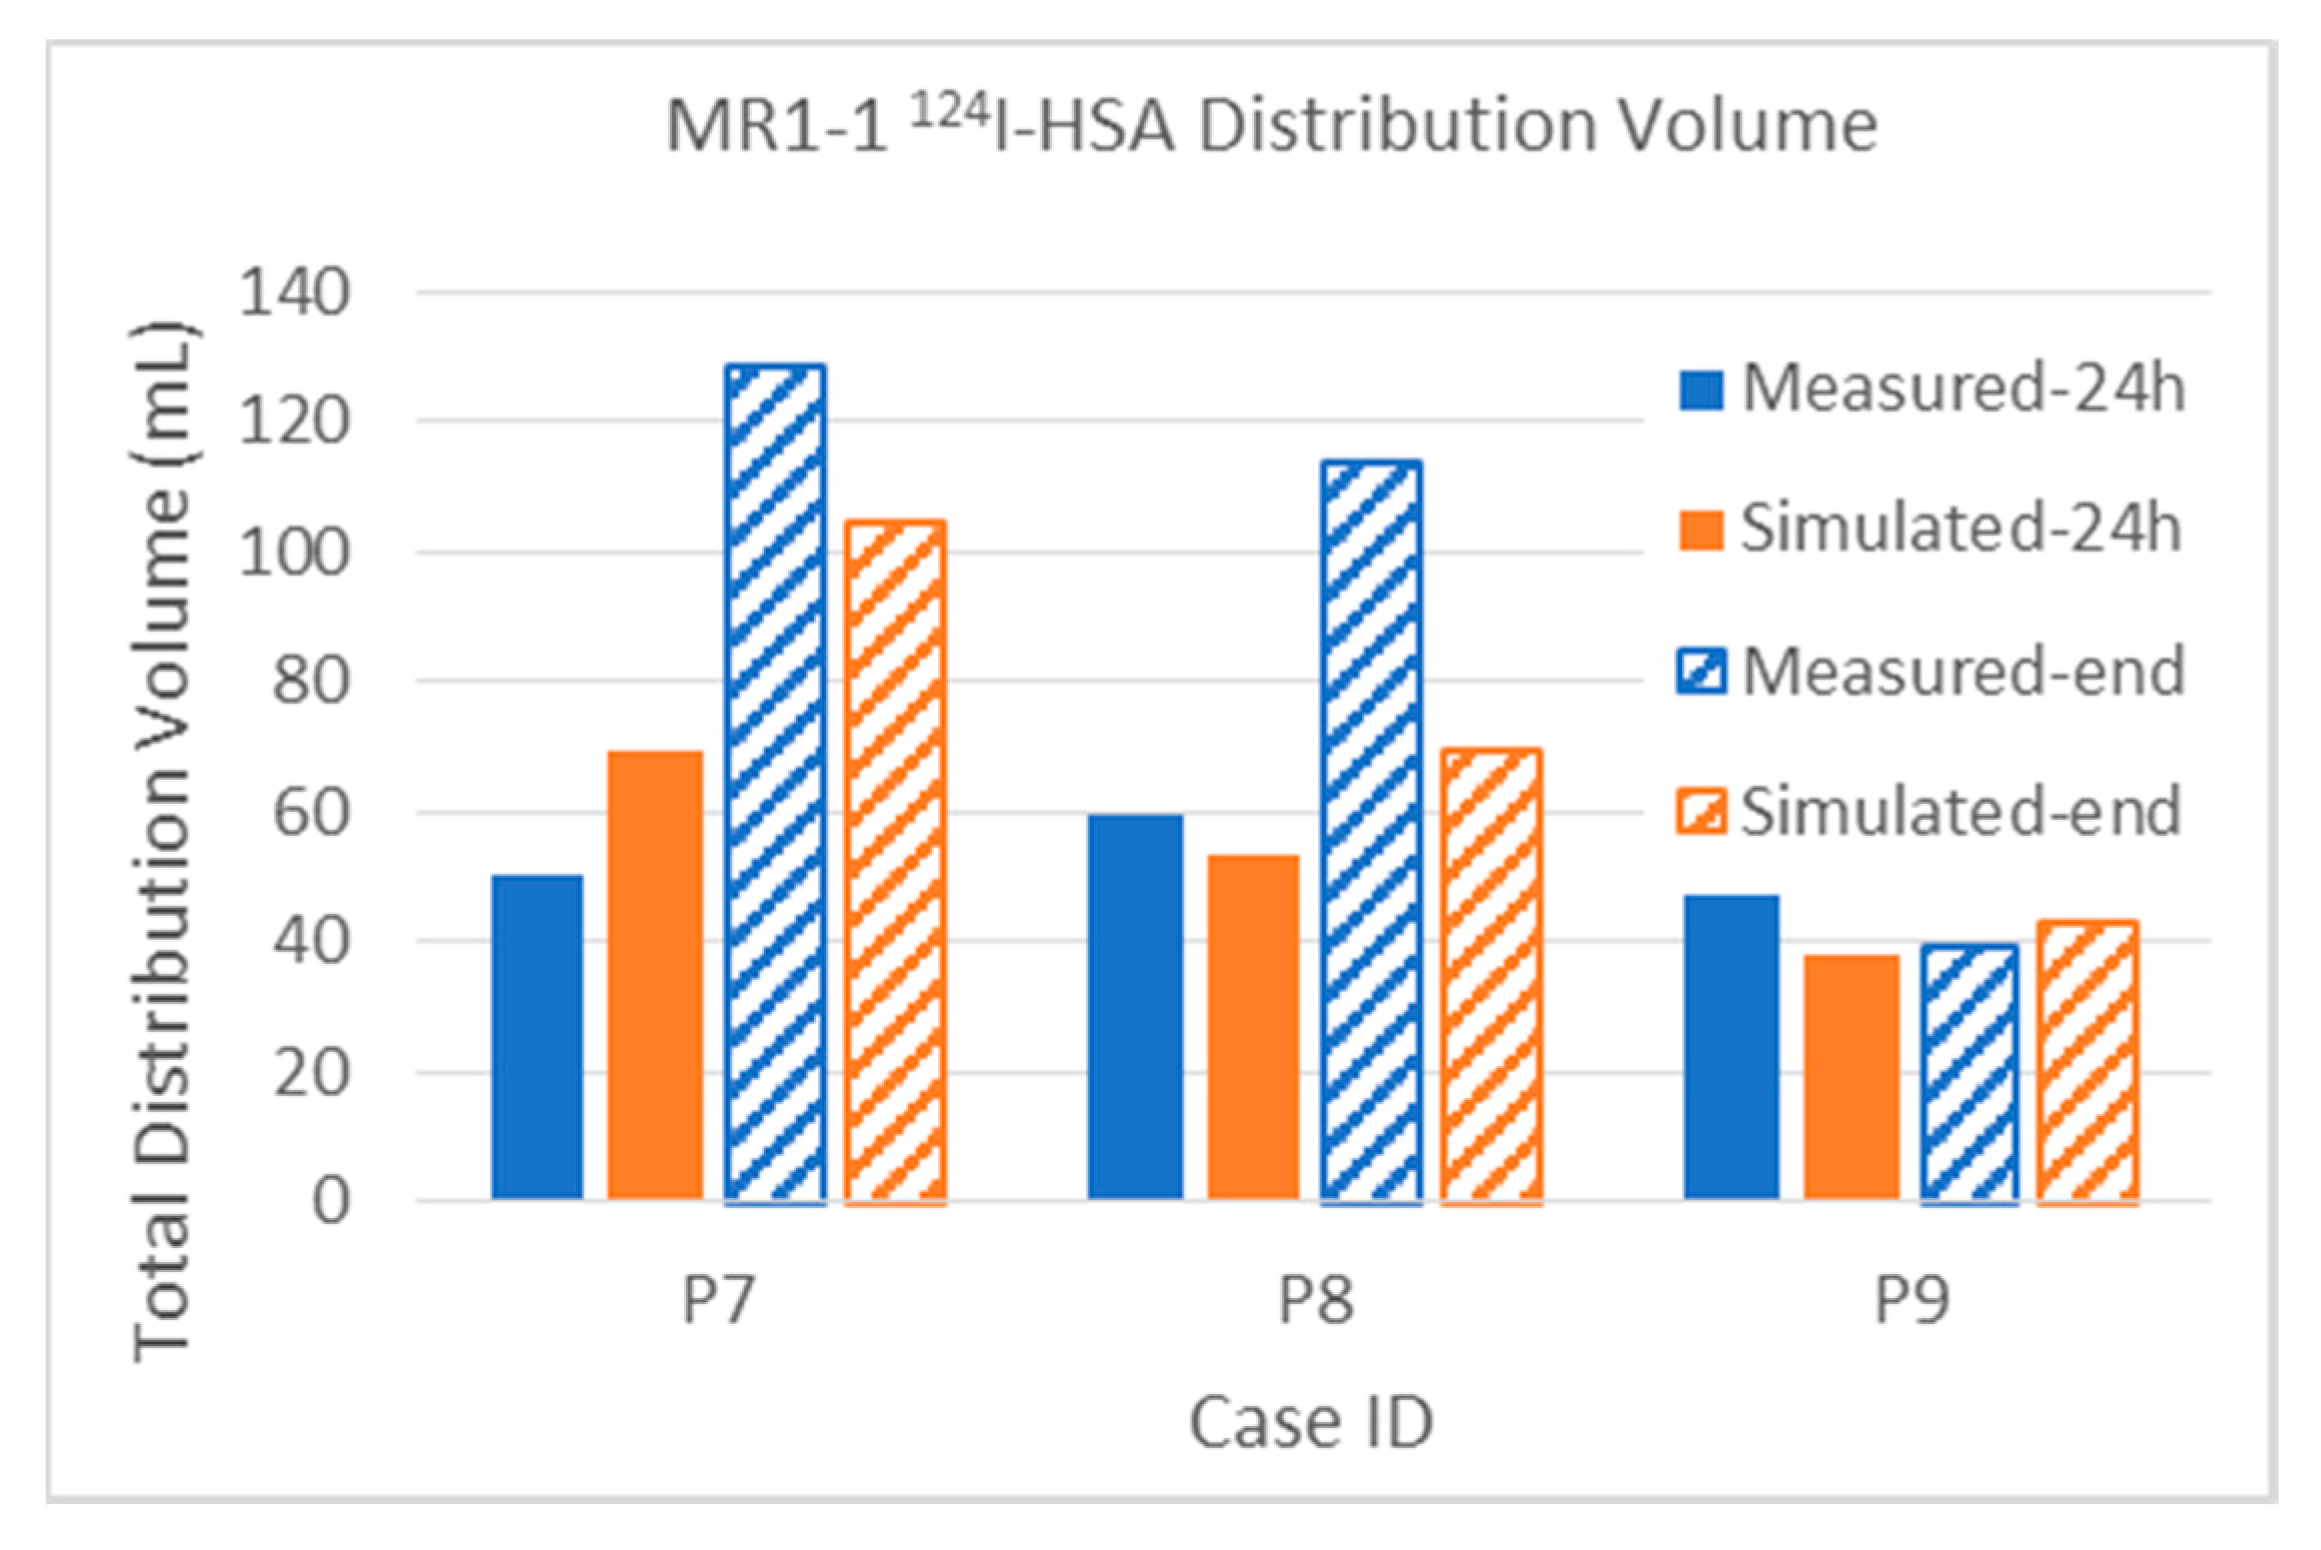

3.2.1. Total Distribution Volume

| 124I | Measured | 15.3 | 21.7 | 31.3 | 73.6 | 50.1 | 128.6 | 38.3% | 54.3% | 18.6% | 43.8% | 40.0 | 168.1 | |

| Simulated | 22.9 | 26.4 | 45.4 | 70.9 | 69.5 | 104.4 | 57.3% | 66.0% | 27.0% | 42.2% | 40.0 | 168.1 | ||

| 124I | Measured | 29.0 | 34.5 | 25.9 | 64.8 | 59.5 | 113.9 | 48.3% | 57.5% | 13.9% | 34.8% | 60.0 | 186.2 | |

| Simulated | 25.7 | 25.8 | 26.8 | 40.2 | 53.6 | 69.2 | 42.8% | 43.0% | 14.4% | 21.6% | 60.0 | 186.2 | ||

| 124I | Measured | 2.1 | 2.2 | 35.2 | 32.5 | 47.3 | 39.4 | 42.0% | 44.0% | 65.7% | 60.6% | 5.0 | 53.6 | |

| Simulated | 1.4 | 1.4 | 28.3 | 30.3 | 37.8 | 42.9 | 28.0% | 28.0% | 52.8% | 56.5% | 5.0 | 53.6 | ||